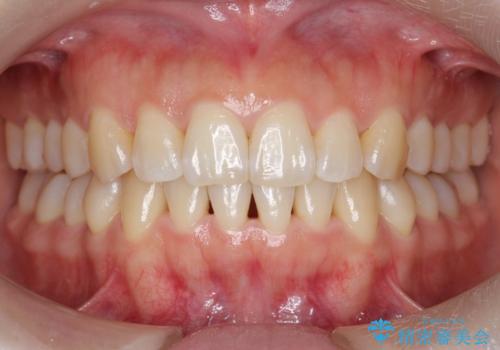

下の前歯のがたつき インビザラインで

- 前歯のがたつきを主訴に来院。

インビザラインで上下の前歯をわずかに削って並べました。

下の歯の叢生を並べると多少ブラックトライアングルがでることがあります。